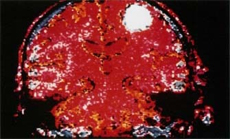

Depresyon 'Tümör'ün Örtüsü OlabilirDepresyonda olduğunu zannedenler dikkat! Hastalığınız beyin tümörü olabilir… İyi huylu tümörler yavaş yavaş gelişiyor ve kişinin ruhsal yapısını etkileyebiliyor…

Depresyonda olduğunu zannedenler dikkat! Hastalığınız beyin tümörü olabilir.

İyi huylu tümörler yavaş yavaş gelişiyor ve bulunduğu yere göre kişinin ruhsal yapısını ciddi bir şekilde etkileyebiliyor.

Beyin ve Sinir Cerrahisi Uzmanı Prof.Dr.Cengiz Kuday: “Beynin frontal yani ön bölgesindeyse tümör, eğer yavaş da büyüyorsa depresyonla karışabilir. Örneklerini çok görmüşüzdür. Veya hareketlerde yavaşlama varsa ve hasta ileri yaştaysa bunama olduğu düşünülür.” dedi. Yıllar içinde bu kişilik bozuklukları had safhaya çıkabiliyor.

Prof.Dr.Kuday: “Kişisel temizliğine dikkat eden biri artık etmez olursa, unutkanlıklar başlarsa, kişisel şahsiyet bozuklukları varsa, örneğin çok düzgün bir insan bir bakarsınız küfürbaz biri olmuştur. Veya tam aksi o kişi içine kapanmıştır. Eğer frontal bölgedeyse; neşeli, girişken, her şeye çok çabuk reaksiyon veren biri haline gelmiştir.” diye konuştu.

Bu tür durumlarda psikiyatriste değil, beyin cerrahına gidilmesi gerekiyor.